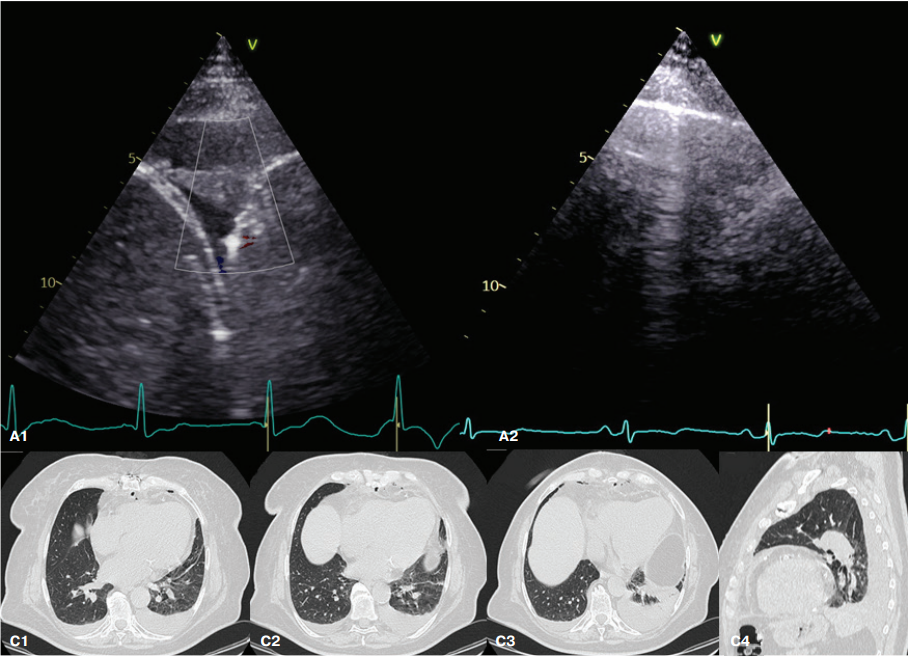

Выполнено УЗИ лёгких (рис. 3 А). По лопаточной линии в 7 межреберье с обеих сторон в проекции нижней доли лёгких визуализируются участки консолидации размерами справа 17,6×24 мм, слева 34×38 мм однородной эхогенности, аваскулярные; подвижность легких незначительно снижена. Около зон консолидации с обеих сторон — множественные тонкие (от 2 до 5 в поле зрения) В-линии. В плевральных полостях жидкость с обеих сторон (справа 120 мл, слева 370 мл). Таким образом, выявлен профиль аваскулярной консолидации нижней доли легких малых размеров, более характерный для ателектазов, двусторонние легочный интерстициальный синдром и гидроторакс.

Проведена КТ ОГК (рис. 3 С). Обнаружена жидкость в плевральных полостях (справа 130 мл, слева 260 мл), частичное коллабирование 9, 10 сегментов правого и 8-10 сегментов левого лёгкого, тяжи по типу субсегментарных ателектазов в S5, S8 слева. Нарушение гемодинамики в малом круге кровообращения по смешанному типу (лёгочно-венозная гипертензия 2 степени, лёгочно-артериальная гипертензия 2 ст.). Диагноз пневмонии не подтвердился. Системная антибактериальная терапия не проводилась, пациентка выписана на 9 сут. после коронарного шунтирования (4 сут. после наложения вторичных швов).

Рис. 3. Лучевые методы исследования легких пациентки П.

Примечание: А — УЗИ (А1 — правая задняя нижняя зона, В-режим, А2 — правая задняя нижняя зона, режим ЦДК), С — спиральная КТ ОГК (С1, С2, С3 — аксиальные проекции в легочном окне на уровне базальных сегментов, С4 — сагиттальная проекция в легочном окне левого легкого).